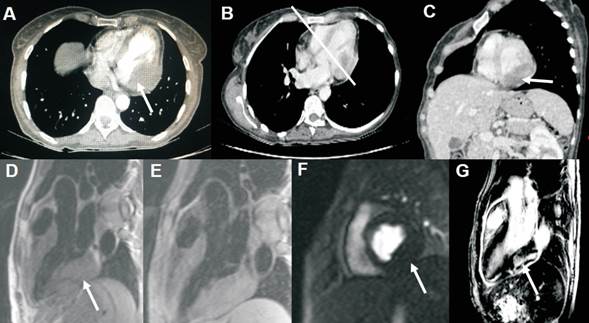

A posteriori, se realiza una tomografía computarizada (TC) de tórax, abdomen y pelvis (figura 4), que muestra una masa de densidad heterogénea, con sectores hipodensos en su interior, situada a nivel de la pared inferolateral del VI; nódulo sólido en espacio subpleural derecho; a nivel abdomino-pélvico se observan los hallazgos ya conocidos. Se realiza una resonancia magnética cardíaca (RMC) que evidencia: FEVI: 64%, tumor cardíaco que infiltra la pared inferolateral basal del VI (que tiene como límite superior el surco AV), de 5 x 3 cm, con infiltración pericárdica y extensión al pericardio adyacente. Dicho tumor es isointenso en las secuencias SSFP, isointenso en T1 (con y sin fat-sat), heterogéneamente hiperintenso en T2, asociado a muy escasa o nula hiperintensidad en la perfusión y heterogéneo en la secuencia de realce tardío. Ante estas características tisulares, se plantea como primer diagnóstico un sarcoma indiferenciado.

Figura 4: Panel superior con imágenes tomográficas, donde se observa en A: corte transversal del tumor (flechas) sin captación de contraste, en B: corte transversal, donde se marca la posición del corte sagital del tumor observada en C (línea blanca). En el panel inferior se ilustran diferentes secuencias de la RMC: D corresponde a T1 siendo la imagen tumoral isointensa respecto al miocardio, E: secuencia T2 heterogéneamente hiperintenso, F: escasa o nula perfusión, y G: realcetardío heterogéneo.

El hallazgo de una masa con aspecto maligno en un paciente portador de una neoplasia ya diagnosticada también sugiere que podría tratarse de una metástasis. Sin embargo, la neoplasia de cuello de útero (carcinoma epidermoide) no se caracteriza por afectación cardíaca, lo que sugiere la concomitancia de dos tumores primarios. Este hecho no es infrecuente. Aunque la BEM podría confirmar el tipo histológico, en muchos casos no es diagnóstica. La TC, realizada en este caso para valoración extracardíaca, es una técnica subóptima para la caracterización tisular, siendo la RMC la técnica de elección. Dicha técnica proveyó una gran aproximación al diagnóstico de la masa, además de sellarnos su malignidad, y nos permitió su valoración cuantitativa debido a su mejor resolución temporal y espacial, así como un mejor contraste de tejidos. Con las secuencias de cine (SSFP), la RMC permite evaluar la función cardíaca. La intensidad de la señal de las masas cardíacas en las secuencias espín-eco (T1 y T2) se compara con la intensidad de señal del miocardio, lo que permite detectar de inmediato anormalidades en el tejido cardíaco y su caracterización tisular. Las secuencias de perfusión permiten evaluar la vascularización tumoral. Finalmente, con el realce tardío se completa la caracterización tisular, que dado la heterogeneidad en este contexto, nos marca la malignidad lesional(4).

Ya desde el año 2003, Hoffman y colaboradores evaluaron las propiedades de los tumores cardíacos mediante RMC y encontraron que su interpretación tenía muy buena precisión diagnóstica para determinar malignidad. Luego, se fueron identificando particularidades específicas a cada tumor. Así, un tumor con las características tisulares encontradas en esta paciente lo identifican como un sarcoma indiferenciado(5).